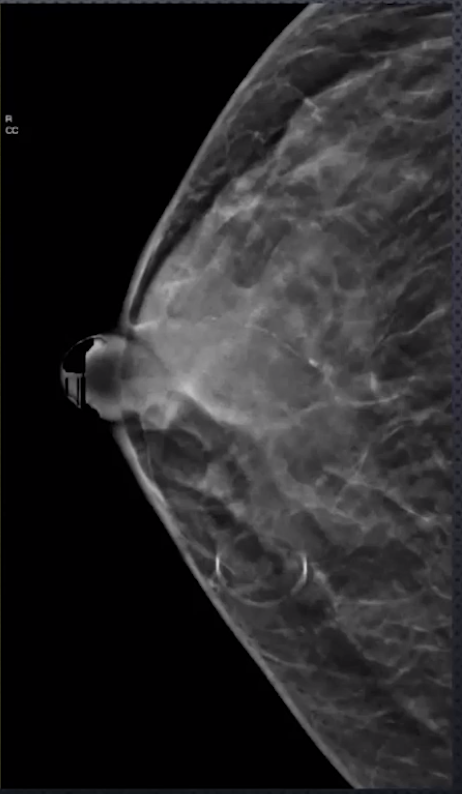

Craniocaudal (CC)

• Patient faces machine

• Images posterior and superior breast very well

• Compressed in the axial plane